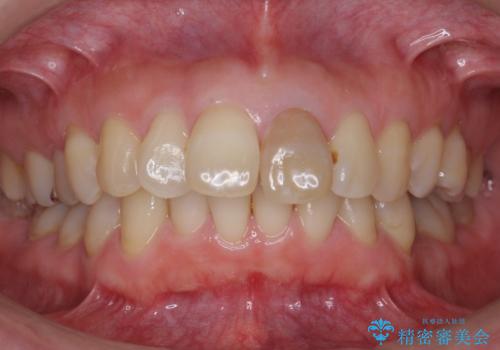

変色した前歯をセラミックでひっこめたい

- 前歯の色と、前突感を気にして来院。

全体的な矯正治療をすすめましたが、ご希望されませんでした。

左上の前歯の神経が失活(死んでいた)していたため、神経の治療を行いました。

また、右上の前歯を下げるため、便宜的に神経を取る治療を行いました。

結果、気になっていた色と角度が良くなり、大変喜んでいただけました。

右上1はひっこめた量が大きかったため、反対側の1番と切端をそろえるのに、多少長さは長くなりました。

右上2、左上2の補綴も提案はしましたが、最小限の本数で行っていくことになり、右上2の捻転(歯のねじれ)はそのままとなっております。